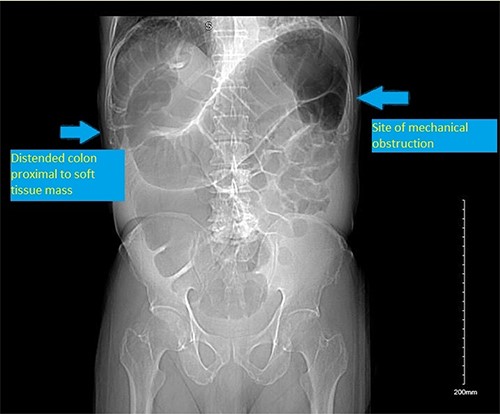

CT scan scout showing distended colon proximal to a soft tissue mass/ shadow at the splenic flexure.